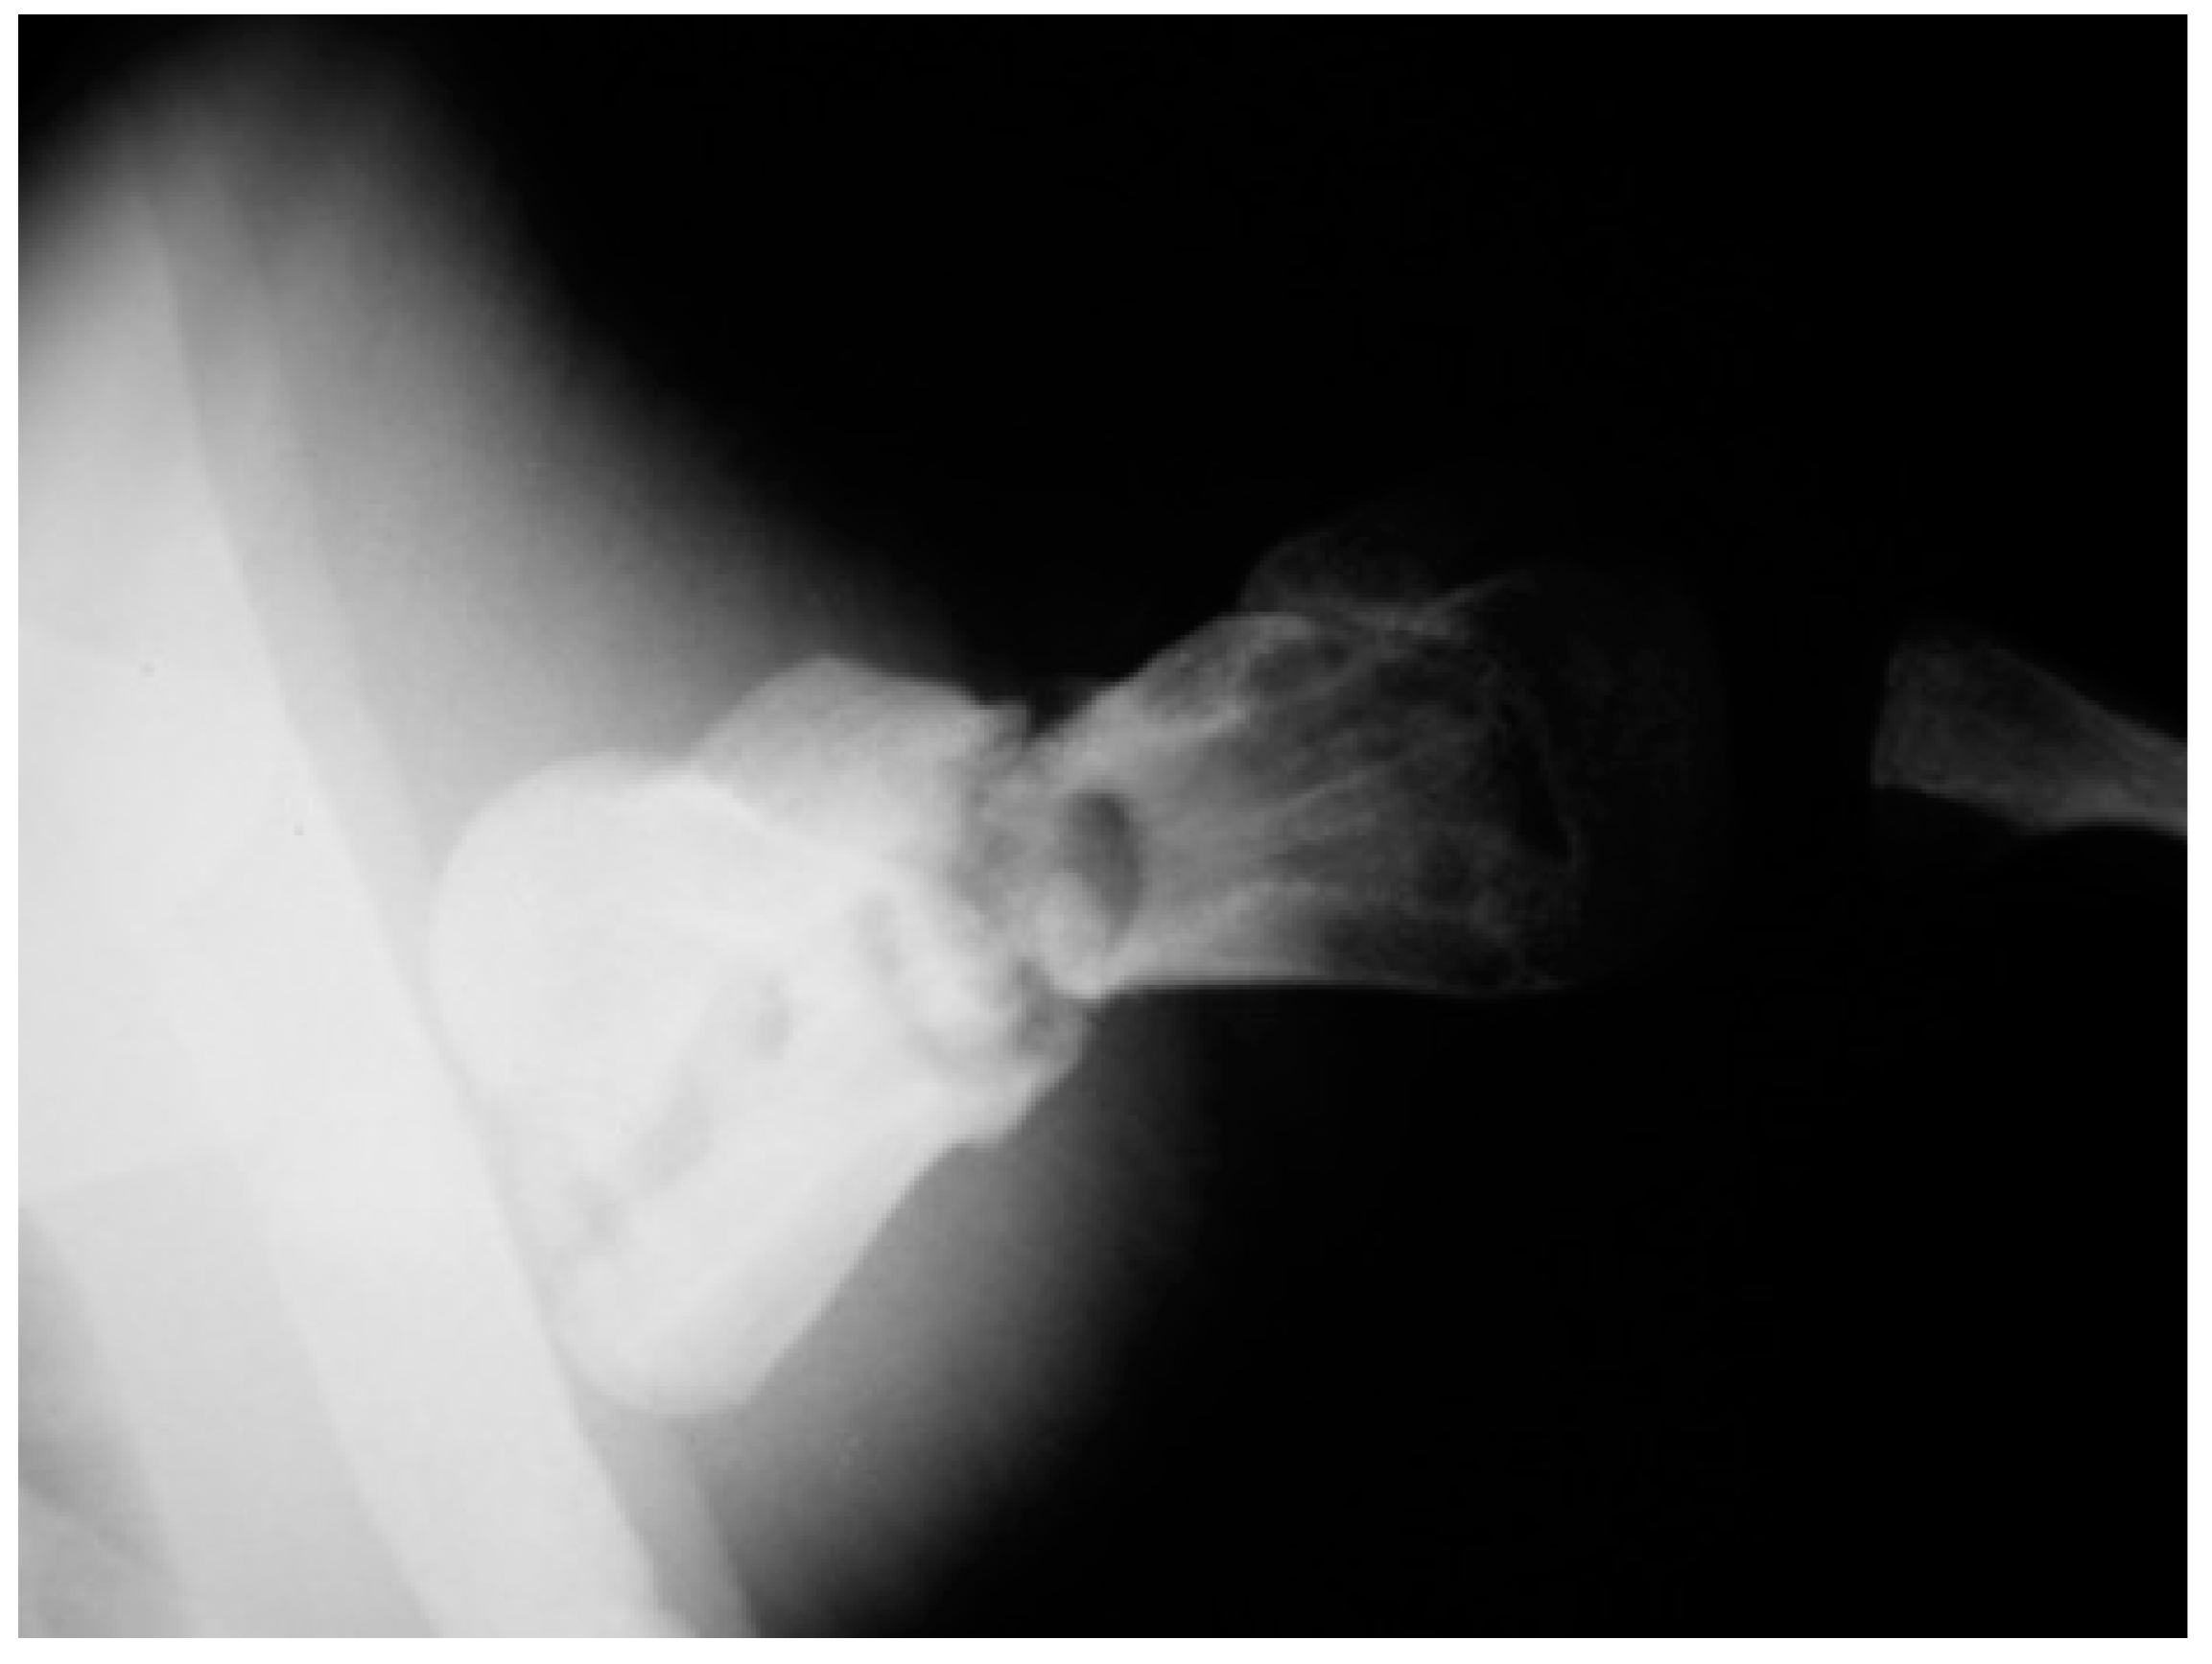

The post-operative radiographic examination confirmed the correct reduction of the diaphyseal fracture, bone realignment, and the good fixation of the detached distal epiphyseal stump (Figure 3). Fifty days later, the X-ray follow-up showed persistent stability of the joint and bone sclerosis, near the diaphyseal fracture site. After 70 days, the turtle could swim and move around comfortably; radiographic examination showed a better filling of the diaphyseal fracture line and almost complete repair of the epiphysis (Figure 4). Four months after surgery, the animal was in good general condition and had recovered the right front flipper’s normal function. Radiography showed a complete repair of the epiphyseal fracture and remodeling of the normal bone architecture, while the diaphyseal fracture still lacked unifying bone callus tissue (Figure 5). After one year, the flipper showed complete clinical recovery without signs of pain, and radiologically the fracture site was fixed, showing signs of remodeling of the fracture stumps, areas of thickened fibrous tissue, but still no appreciable unifying bone callus (Figure 6a). The good positioning and tightness of the means of fixation were radiologically confirmed, but the surrounding bone reabsorption and decalcification processes were evident. Removal of the intramedullary pins was deemed necessary. Radiograms performed after removal of the pins showed the presence of calcified sites within the tissue interposed between the two bone stumps (Figure 6b). Two years after the procedure, radiographic follow-up demonstrated a better filling of the fracture line and further remodeling of the stump margins (Figure 7).

Figure 3. Caudocranial radiograph of the anterior right flipper: postoperative follow up examination.

Figure 4. Two-month follow-up performed in caudocranial view of the anterior right flipper showing the filling of the diaphyseal fracture line.